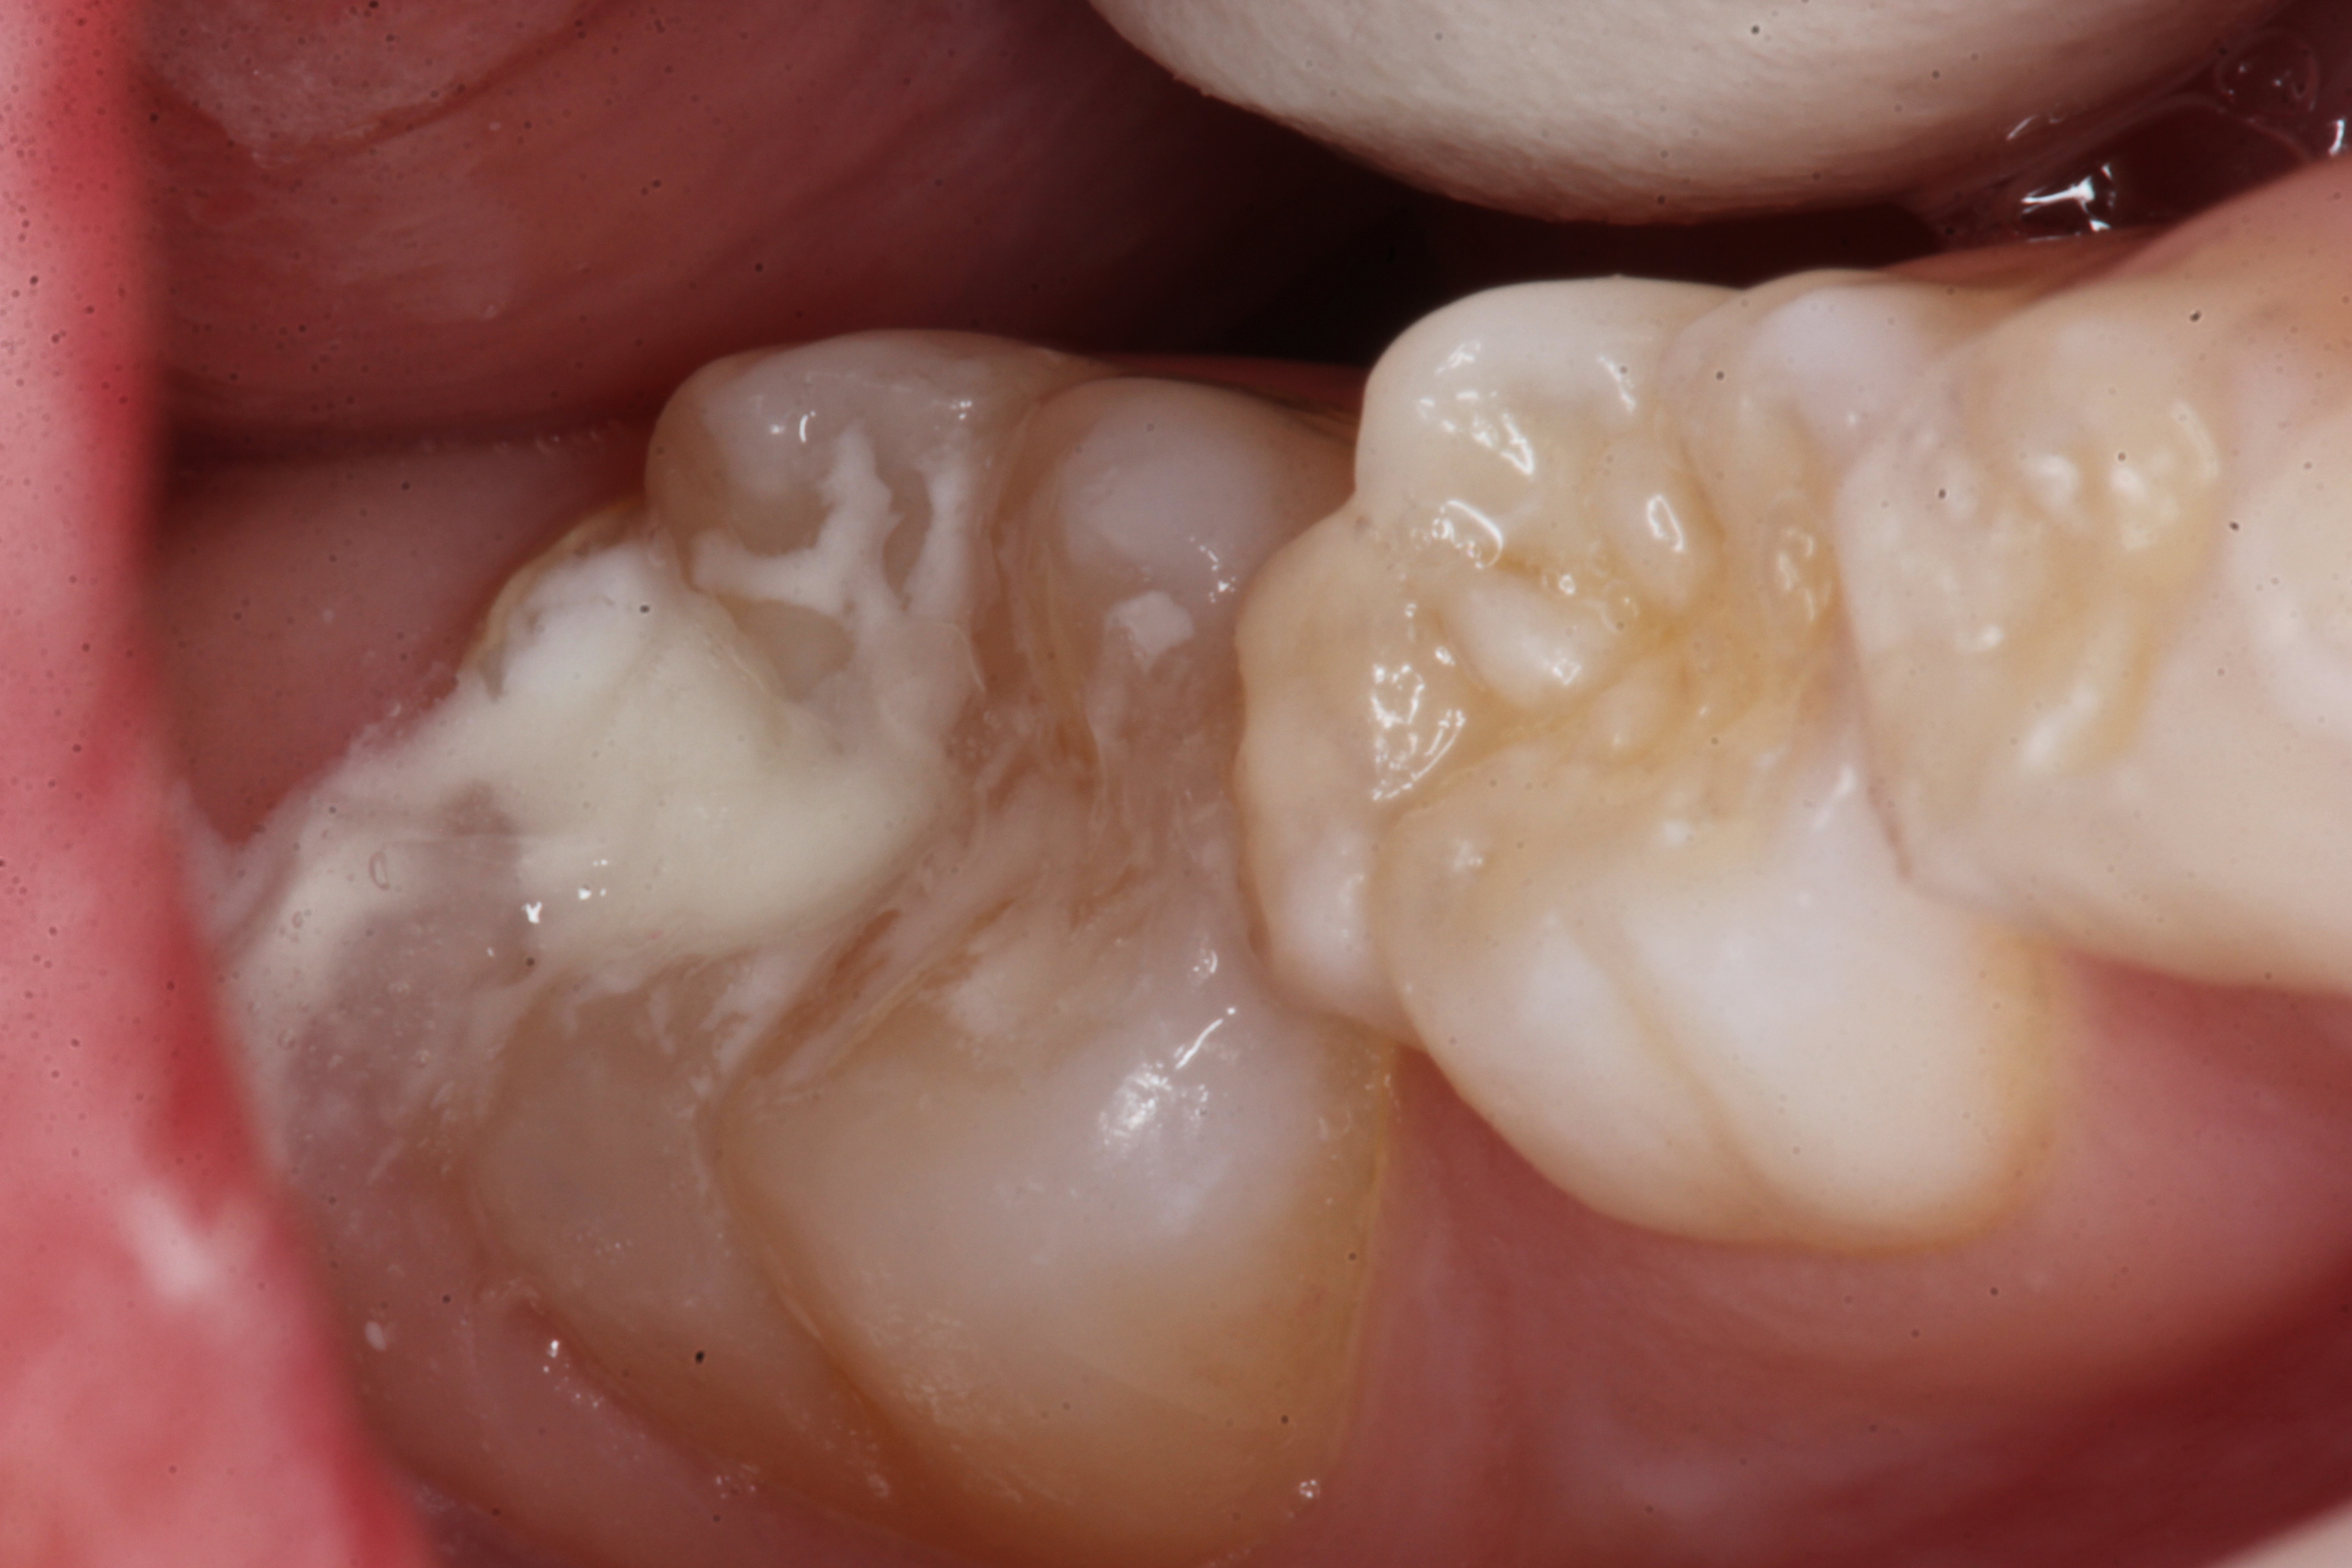

若い子の歯科治療シリーズ1.8(頬側面カリ… 2025.09.20